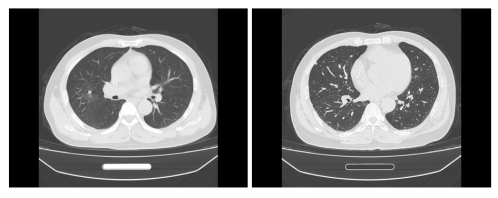

2022.07胸腹部CT:右肺下叶见片状实变影;肝左外叶上段结节,考虑左肝新发转移瘤。

2022.08PET-CT见肝左外叶糖代谢增高,SUV值为10.8。粒子植入术后膈肌上方局限性放射性肺损伤,自行好转。

image.png

图8 影像评估提示肝左外叶糖代谢增高

图9 影像评估提示肝左叶转移瘤较前增大

图12 影像评估提示肝左叶转移瘤较前缩小